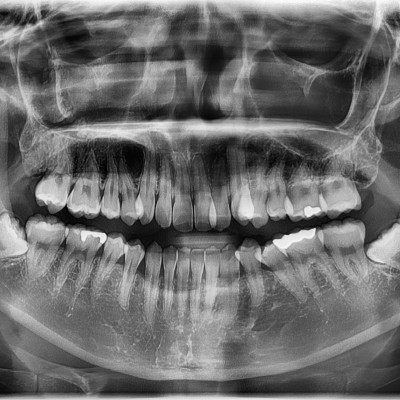

#38 사랑니 발치 N새글 #38 사랑니 발치 구강 외과 전문의가 당일 발치했습니다. -----------------------------..